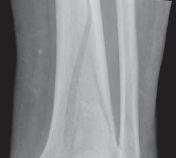

The diagnosis of tibial plafond fracture is initially evaluated with three radiographic views of the ankle (anteroposterior [AP], mortise, and lateral; FIG 4A,B).

These views should be repeated after all “reductions,” including application of temporizing external fixation.

CT scans have been clearly shown to improve a surgeon’s understanding of the injury ( FIG 4C) and are critical to preoperative planning for complex injuries.15

For displaced, comminuted pilon fractures, the best time to obtain a CT scan is after temporizing external fixation is performed ( FIG 4D), when the fracture is brought out to length with traction. This tends to grossly reduce many parts of the fracture, making the pathoanatomy of the injury more understandable (FIG 4E,F).